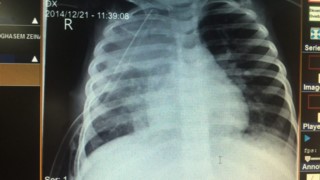

تشخیص:

عفونت قارچی